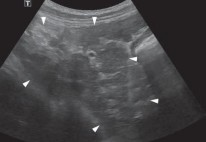

Hình 4.16. Hình ảnh chó bụng báng nước (mũi tên) | Hình 4.17. Hình ảnh siêu âm xoang bụng tích dịch (mũi tên) |